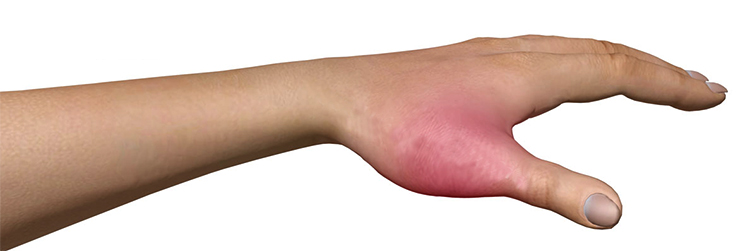

Формирование отеков в области полученного повреждения

Что касается ушибов, то главное отличие перелома от ушиба пальца ноги заключается в мгновенном образовании значительного отека в области удара. В тоже время он может полностью исчезнуть или уменьшиться в течении двенадцати часов после времени полученной травмы.

1. Образование припухлости в месте получения повреждения.

2. Изменение цвета пальца (он может покраснеть или посинеть).

3. Боль при попытке пошевелить пальцем.

4. Образование гематомы, которая может быть светло-синего или черного цвета.